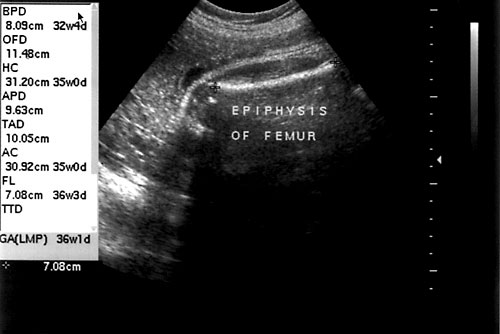

Normal fetal hand with four fingers and thumb on right side of photo (left). Normal fetal feet with five digits on each with normal anatomy (right).- Femur length — accurate for measuring gestational age.

- Most accurately measured perpendicular to angle of insonation. (Goldstein RB, Filly RA, Simpson G. Pitfalls in femur length measurements. J Ultrasound Med 1987;6(4):203-7. & Jeanty P, Rodesch F, Delbeke D, Dumont JE. Estimation of gestational age from measurements of fetal longg bones. J Ultrasound Med 1984;3(2):75-9.)

Proper measurement of femur. - Distal epiphysis not included in measurement. (Mahony BS, Filly RA. High-resolution sonographic assessment of the fetal extremities. J Ultrasound Med 1984;3(11):489-98. & Abrams SL, Filly RA. Curvature of the fetal femur: A normal sonographic finding. Radiology 1985;156(2):490.)

Femur at 36 weeks with epiphysis seen to left of photo at arrow.

- Femur length — accurate for measuring gestational age.